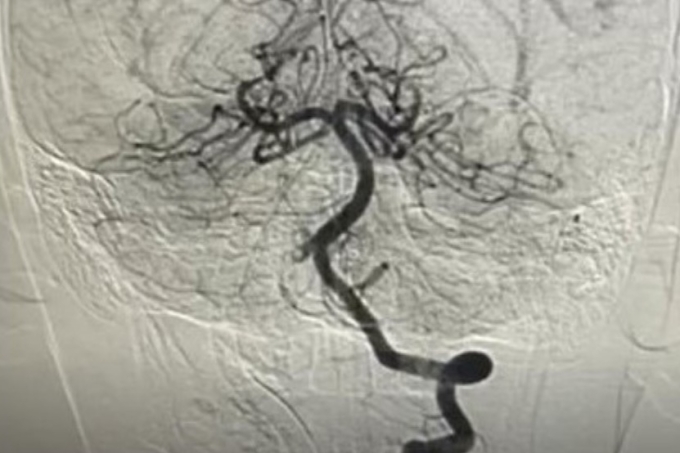

Bé 10 tuổi suýt liệt vì đột qụy.

3. Bé 10 tuổi suýt liệt vì đột quỵ

Trước nhập viện, bé tham gia hoạt động thể thao, không ghi nhận chấn thương hay va đập. Tuy nhiên, sau đó xuất hiện các triệu chứng thần kinh cấp tính như đau đầu dữ dội, nôn ói nhiều, rối loạn đi đứng và yếu dần nửa người trái.